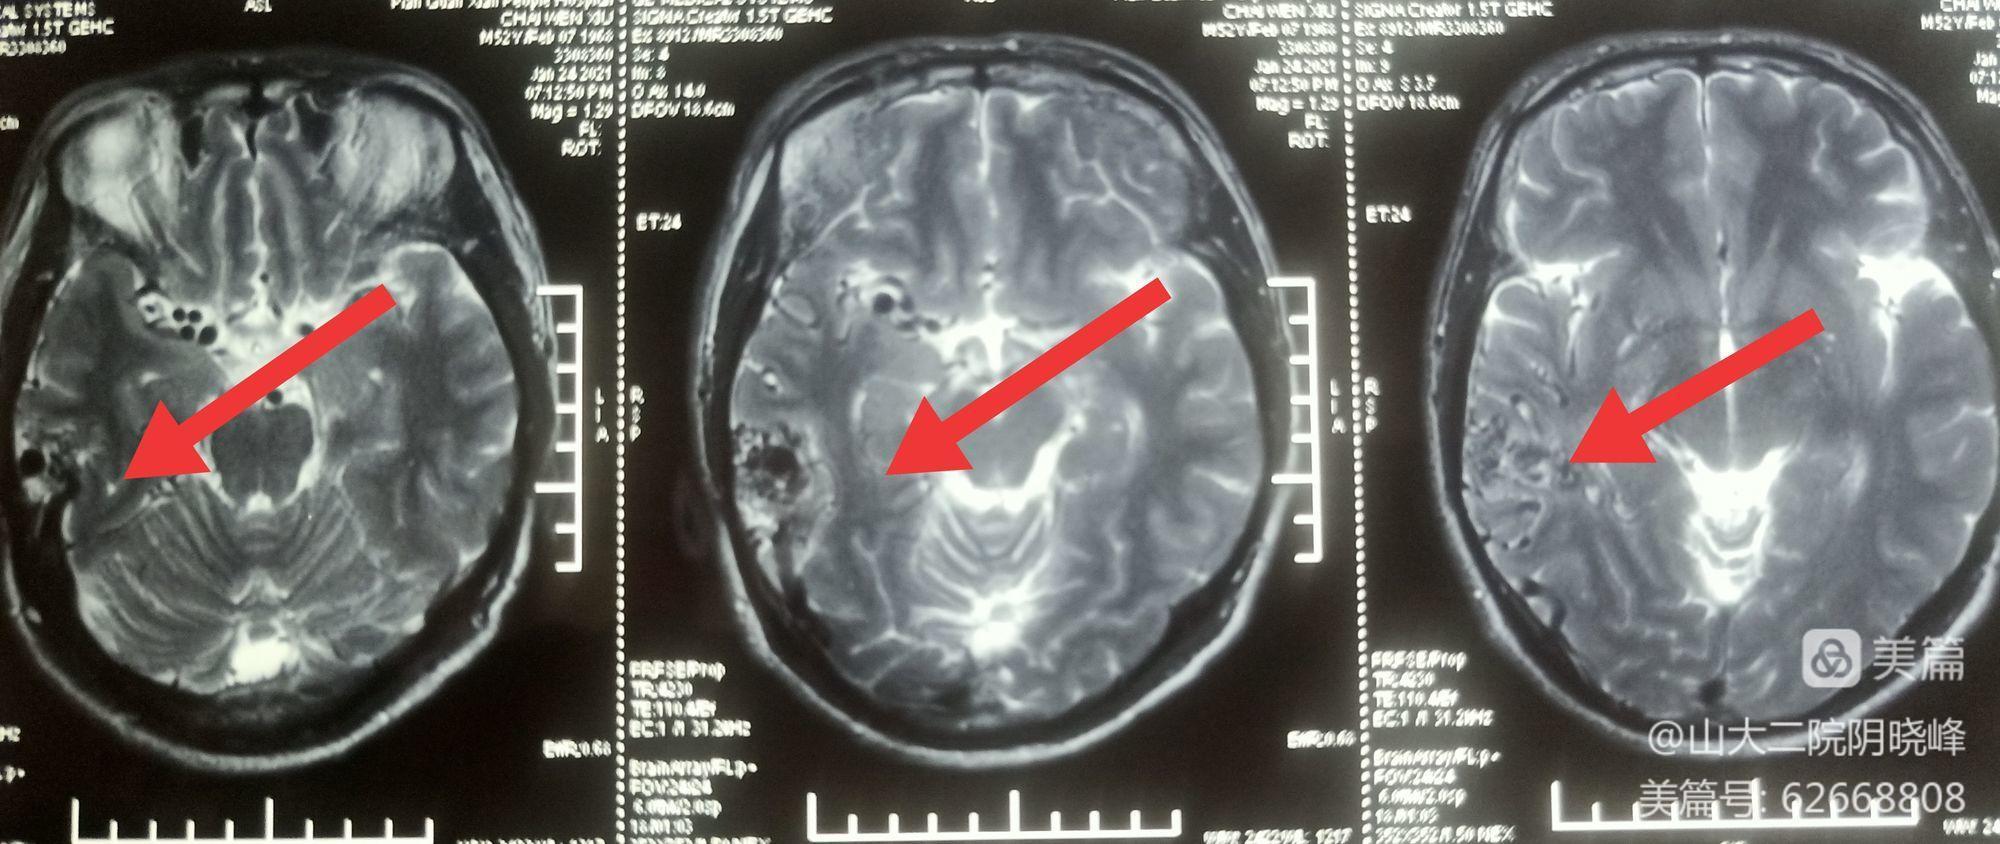

辅助检查:头颅核磁:右侧颞枕交界区可见迂曲流空信号影

术前头颅核磁:右侧颞枕交界区可见迂曲流空信号。